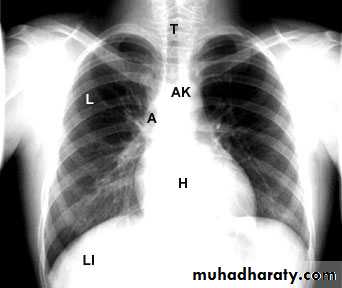

NORMAL PA view